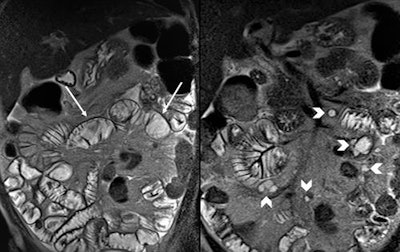

Coronal T2-weighted half-Fourier acquisition single-shot turbo spin-echo images at cavitating mesenteric lymph node syndrome in a case of refractory celiac disease, which display decrease in number of jejunal folds (arrows) along with cystic mesenteric lymph nodes (arrowheads). All images courtesy of Dr. Amir Reza Radmard.

Coronal T2-weighted half-Fourier acquisition single-shot turbo spin-echo images at cavitating mesenteric lymph node syndrome in a case of refractory celiac disease, which display decrease in number of jejunal folds (arrows) along with cystic mesenteric lymph nodes (arrowheads). All images courtesy of Dr. Amir Reza Radmard.A measure of 1,500 mL of polyethylene glycol (PEG) was administered orally at three aliquots (each aliquot: two packets, 25 g, of PEG dissolved in 500 mL of water, consumed in 15 minutes). A single dose of metoclopramide (10 mg) with the first aliquot to promote gastric emptying, and if bowel distension was not satisfactory, an additional 500 mL of water was given over the next 15 minutes. To decrease bowel peristalsis, IV hyoscine N-butyl bromide (20 mg) was administered when the distension of the small bowel was satisfactory on the first sequence (coronal T2-half-Fourier acquisition single-shot turbo spin-echo, HASTE).

- In a patient with refractory celiac disease who has experienced recent deterioration of signs and symptoms, the presence of enlarged cystic mesenteric lymph nodes in addition to the typical findings of Celiac disease (fold reversal pattern) can help to make a diagnosis of cavitating mesenteric lymph node syndrome.